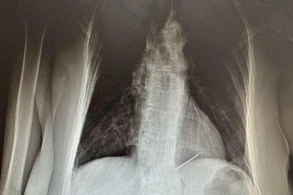

Yakutiyada cərrahlar 57 yaşlı xəstənin ağciyərindən tikiş iynəsini çıxarıblar.

“Medicina” xəbər verir ki, Verxnevilyuski rayonunun sakini döş qəfəsindəki ağrılara görə həkimə müraciət edib.

Görüntülərdə 57 yaşlı xəstənin ürəyi və sol ağciyəri nahiyəsində iki iynə tapılıb.

Məlum olub ki, qadın tikiş iynələri ilə özünü deşib və onlardan biri ürək əzələsinə ilişib.

Lakin o, xəstəxanaya yalnız iynə sol ağciyərinə düşəndən sonra gəlib.

Yad cismin çıxarılması əməliyyatını Yakutskdan Verxnevilyuy Mərkəzi Rayon Xəstəxanasına gələn cərrah Aisen Vasilyev həyata keçirib. İğne kiçik bir kəsiklə uğurla çıxarıldı. Xəstə hazırda evə buraxılmağa hazırlaşır.

Ürək əzələsindəki ikinci iynə ilə bağlı Yakutiyanın Ürək-Damar Mərkəzinin mütəxəssisləri ilə məsləhətləşmə aparılır.

Qadını əməliyyat edən cərrah qeyd edib ki, iynə iki il əvvəlki rentgendə görünüb və xəstənin dediyinə görə, ona heç bir narahatlıq yaratmayıb.